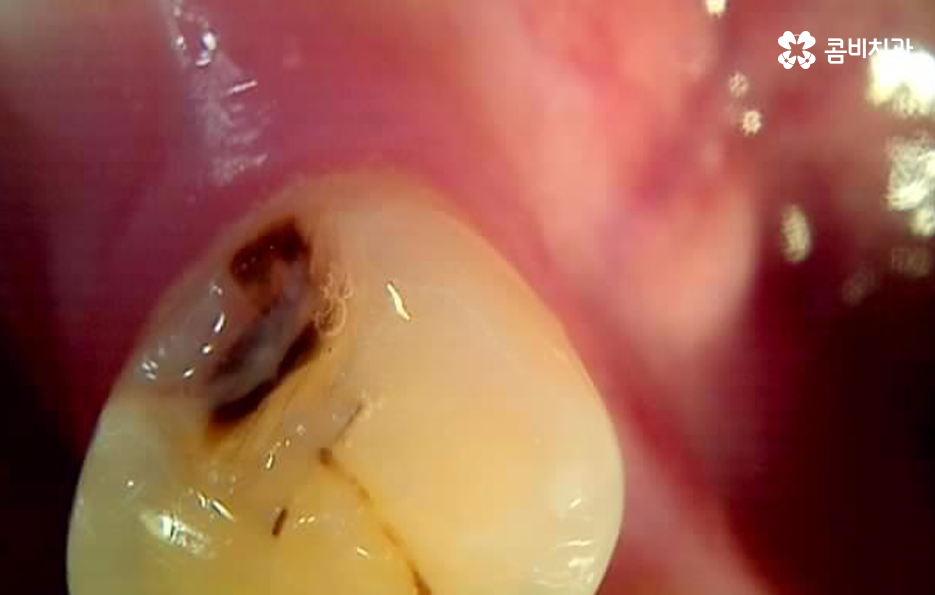

치아의 형태를 보면 치아는 굴곡이 있고 깊게 파인 부분이 있는데 어릴 때 주로 발생되는 충치는 치아의 홈에서 시작되는 경우가 많기 때문에 치아의 홈을 메우는 실란트 치료를 받는 경우가 많이 있어요

위 사진처럼 치아의 홈부분에서 시작되는 충치는 칫솔질을 잘하면 성인 이후에 어느정도 예방이 되지만 치아 옆 부분과 잇몸 쪽에 치석이 많이 쌓여 있는 것을 확인할 수 있는데요

치아와 잇몸에 쌓여 있는 치석은 잇몸도 내려앉게 만들 수 있고 치아의 뿌리 쪽 부분이 외부에 드러나게 되어 충치가 치아 하단부에 발생하면 신경과 가깝기 때문에 신경치료로 이어지는 사례도 많이 있어요